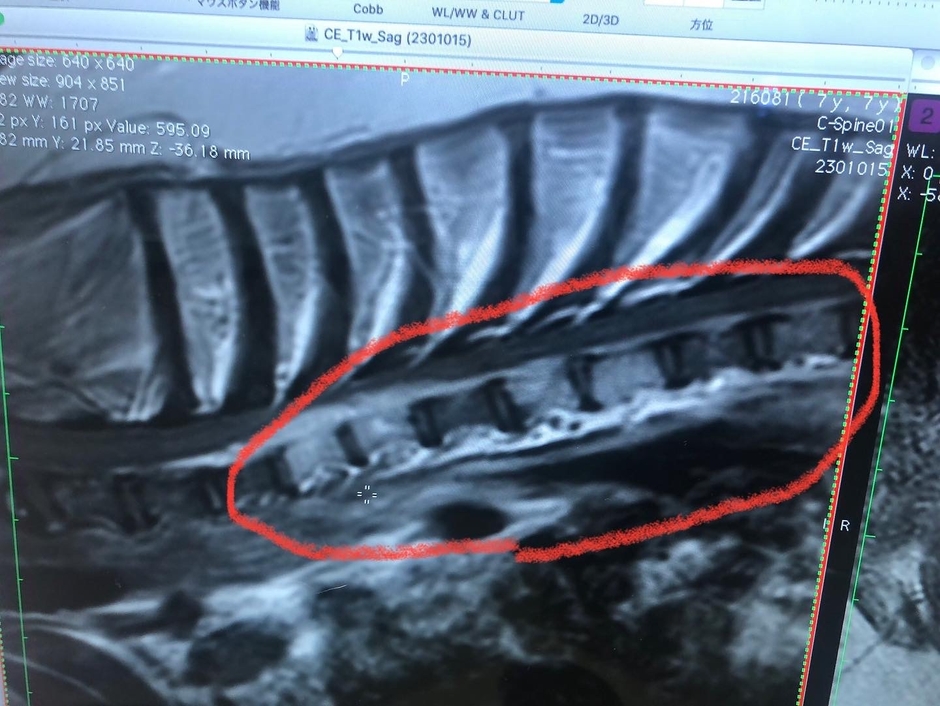

※腫瘍部を拡大して画像です。縦の白い柱が、腫瘍に侵されてしまった骨です。

左側、白い骨の上部に細長い雲の様に見える物も腫瘍です。

MRI検査で、頚椎6番の骨が腫瘍に侵されてしまい、骨に穴が空き、そこから腫瘍があふれ出てしまったため、神経を圧追し神経麻痺を引き起こしていました。

※骨に穴が開いているのが確認できます